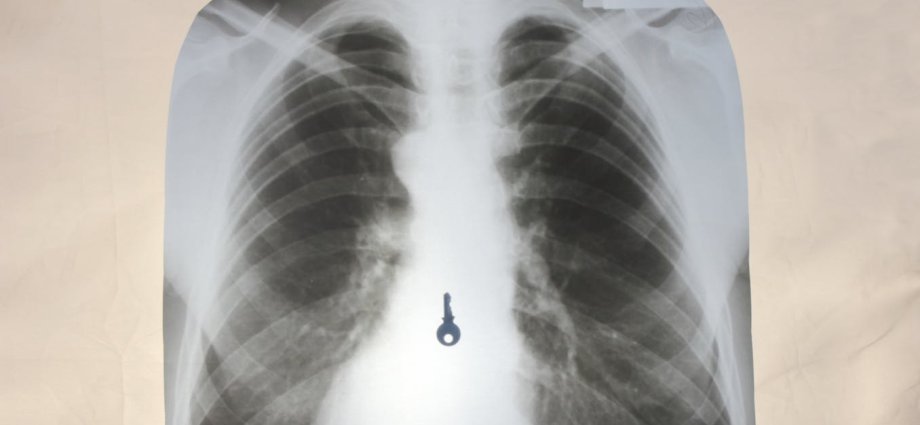

But while in this recent instance the stolen jewels were recovered after naturally passing through the thief’s body, this isn’t always the case when things are swallowed that shouldn’t be. Foreign body ingestion, as it’s called, accounts for approximately 1,500 deaths per year in the US alone.

Although most of the time, ingested foreign bodies pass naturally, around 10-20% of cases require endoscopic retrieval (a camera and small tools entering your mouth to get to your stomach) – and 1% require emergency surgery. In adults, the most commonly ingested foreign bodies are fish or chicken bones. In children, it’s coins, button batteries and toy parts.

Small items, such as earrings, aren’t too difficult for the body to pass if swallowed accidentally or on purpose. This is because the oesophagus, which carries food to the stomach, is up to 3cm in diameter.

But if objects are too large and get stuck in the oesophagus, they can tear and perforate it. A tear to the oesophagus requires immediate medical intervention – without emergency care, this tear has a mortality rate of up to 40%.

The stomach, a J-shaped sac, has a much larger diameter than the oesophagus. It then connects to the small intestines and subsequently the large intestines. But because of the stomach’s unique shape and the way it tightly narrows as it joins the small intestines, objects can easily get lodged in this join.

In one case study, doctors in Iran removed more than 450 metallic items from a man’s stomach – including screws, keys, nuts and other metal parts. These objects weren’t able to pass naturally due to the narrowing of the digestive tract – subsequently building up in the stomach, leading to abdominal pains and digestive issues in the patient that required immediate surgery.

Should an item manage to pass through the stomach, it then has to move through 12 feet of small intestines before entering the large intestines. The appendix is located where these intestines meet – and any foreign objects that enter this tube are unlikely to get back out the way they came. So, this is another site where items can easily become stuck, causing infection and the need for emergency surgical removal.

In one rare case, a diamond earring caused appendicitis in a person who had swallowed it by accident. There are also cases of this happening after screws, stones and pins became lodged in the appendix.

The large intestines, where faeces begin to form, gradually begin to narrow in diameter, especially near the rectum. This makes it even more likely that the intestinal wall may be perforated by foreign objects – particularly sharp things such as the post of an earring or even packets of smuggled drugs.

Perforation of the bowel anywhere through the gastrointestinal tract is a surgical emergency, as it means the contents of the tract – which includes billions of bacteria – can leak into the membrane that lines your pelvis and abdomen. This can cause serious and often fatal infections such as peritonitis and sepsis, which can have mortality rates of almost 50%.